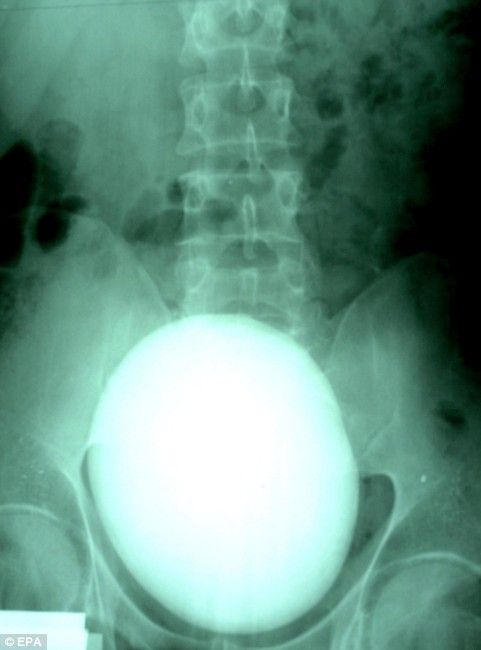

It is horrible to imagine that such thing can be inside of a human body.

It is even more horrible to imagine how it can be extracted from there.

Here’s the story of one kidney stone which weighs only 1 kilogram after the jump.